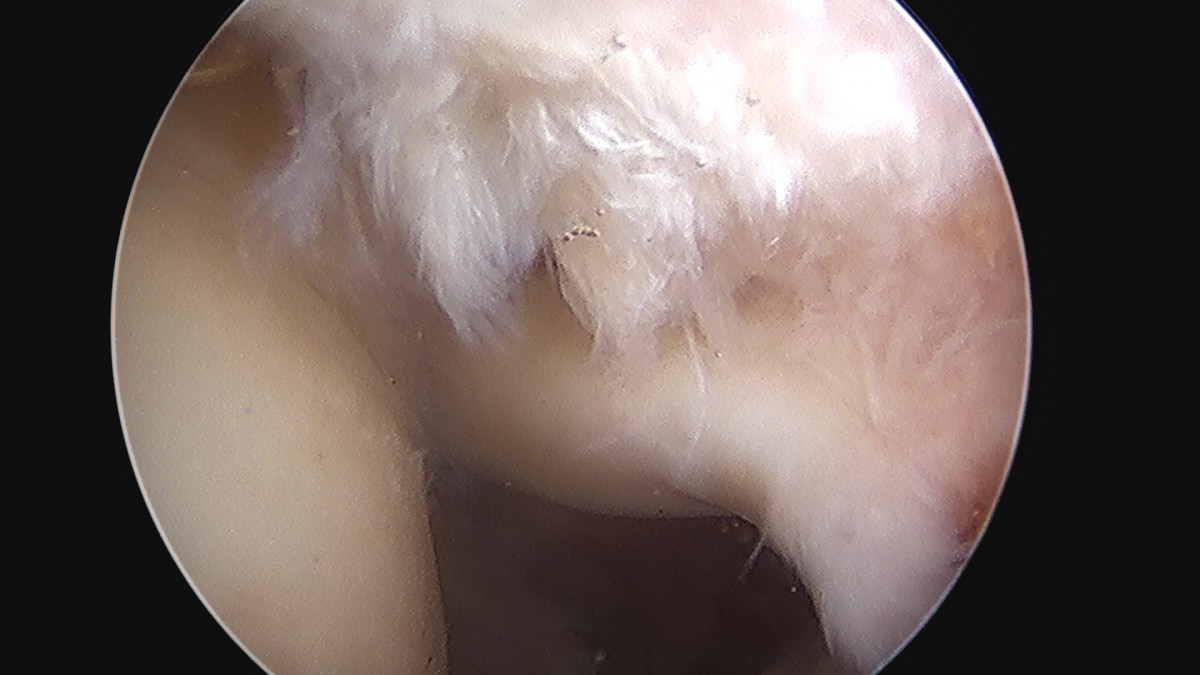

이재상원장님 어깨 이두박건 절제술 정하O 환자

dae765e4d9ac96aee867c9d6292d8784_1758006930_1385.jpg